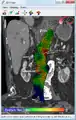

An aneurysm ruptures if the mechanical stress (tension per area) exceeds the local wall strength; consequently, peak wall stress (PWS),[30] mean wall stress (MWS),[31] and peak wall rupture risk (PWRR)[32] have been found to be more reliable parameters than diameter to assess AAA rupture risk. Medical software allows computing these rupture risk indices from standard clinical CT data and provides a patient-specific AAA rupture risk diagnosis.[33][34][35] This type of biomechanical approach has been shown to accurately predict the location of AAA rupture.[34][35][36]

Abdominal aortic endoprosthesis, CT scan, original aneurysm marked in blue